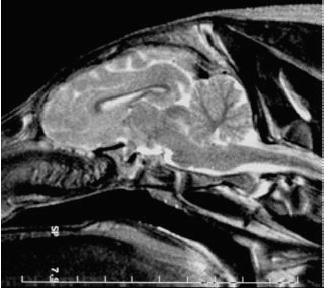

Fig. 25: Magnetic resonance image of the brain of a ~3 month-old piglet of the first litter; metric scale. No differences were apparent between irradiated piglets and sham-irradiated littermates. |

The next step was to test tissue tolerance of the brain in larger animals. The cerebellum of the weanling piglet was used as a surrogate for the radiosensitive human infant cerebellum. Five weanlings in a 47-day-old litter of seven, and eight weanlings in a 40-day-old litter of eleven were irradiated at the ESRF. A 1.5 cm-wide x 1.5 cm-high array of microbeams was propagated horizontally through the cerebella of the prone, anesthetised piglets. Skin-entrance intra-microbeam peak absorbed doses were 150, 300, 425, or 600 Gy. For ~66 weeks (first litter; until euthanasia; Figure 24), or ~70 weeks (second litter) after irradiation, the littermates were developmentally, behaviourally, neurologically and radiologically (Figure 25) normal as observed and tested by experienced farmers and veterinary scientists unaware of which piglets were irradiated or sham-irradiated. These observations give credence to MRT's potential as an adjunct therapy for brain tumors in infancy.